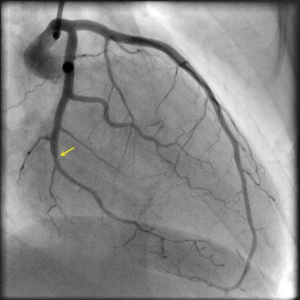

SCAD Angiography

Shown below are animated and static angiography images exemplifying each type of SCAD. For additional angiographic images of SCAD, click here.

Type 2B

Projection angle: 30 RAO, 1 CRA. Type 2B SCAD is seen in OM2.